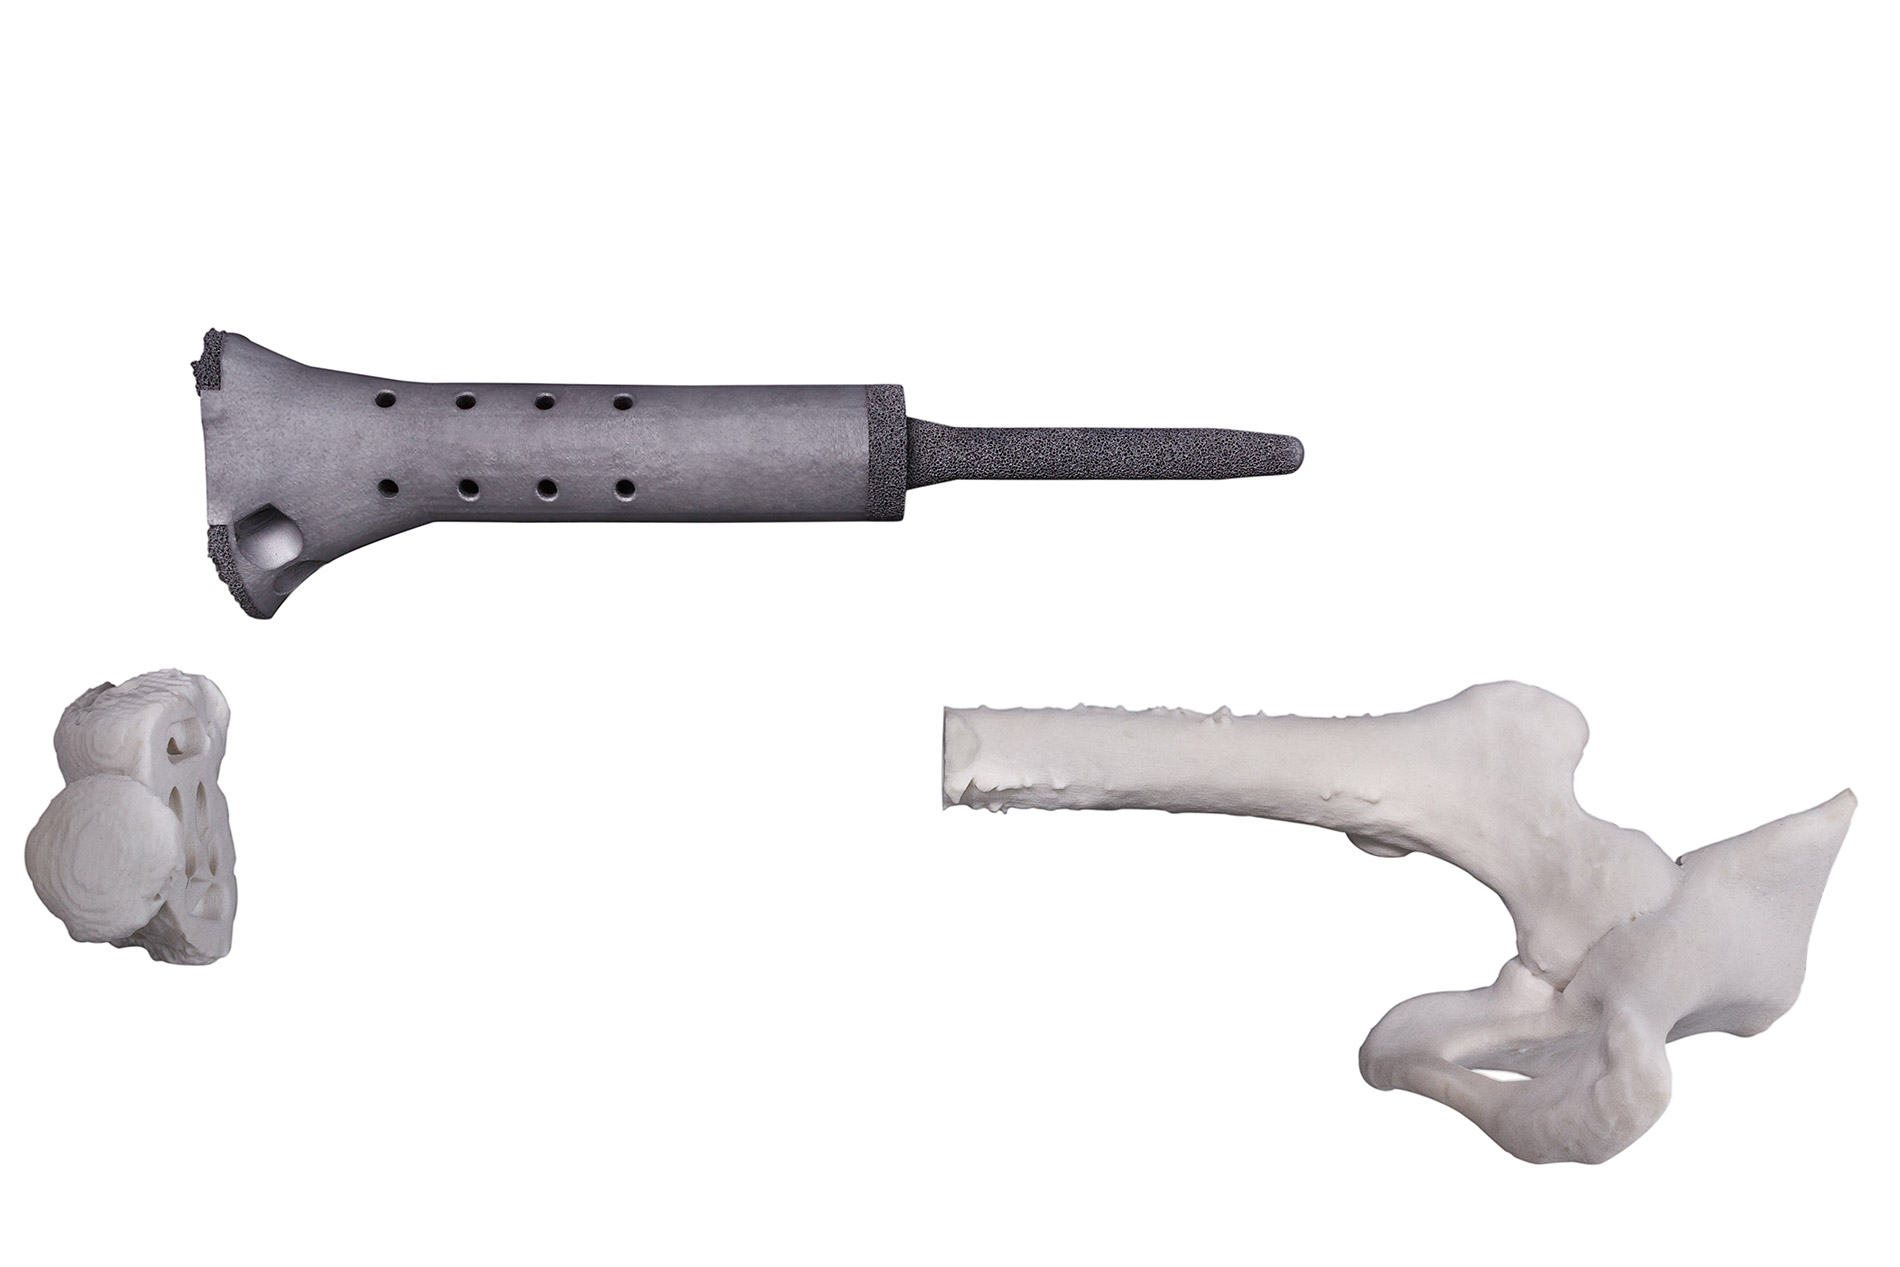

Reproducimos en nuestros implantes de titanio biocompatible la misma trama de cavidades que poseen los huesos del cuerpo humano haciéndolos livianos y extremadamente resistentes

La reconstrucción utiliza como información de entrada imágenes obtenidas por técnicas de diagnóstico (TAC o MRI). A través de un software especializado se procesan las imágenes y se logra modelar en tres dimensiones cualquier región anatómica con patologías diversas.

En el modelado 3D digital se pueden incluir implantes ortopédicos como placas, tornillos, mallas, prótesis, etc., y también modelados en 3D y en tamaño real en relación con el modelo anatómico. De esta forma es posible simular diferentes situaciones con las que el cirujano se enfrentará durante el proceso quirúrgico.

Implantes a medida, impresos en 3D con tecnología TST® (Titanio Trabecular)

2 | Permite la reconstrucción de modelos en tres dimensiones y a tamaño real para lograr un mejor ajuste anatómico.

6 | Se aplica a diferentes regiones anatómicas: cráneo, ATM pelvis, etc.